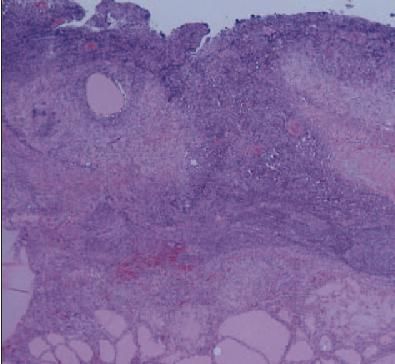

The pathology laboratory reported a chronic active inflammation with an abscess in the base of an adenomatous goiter (AG) (Figure 5).

A microscopic photograph of the thyroid gland specimen after right subtotal thyroidectomy demonstrates chronic active inflammation with abscess formation (hematoxylin-eosin stain, original magnification 40).